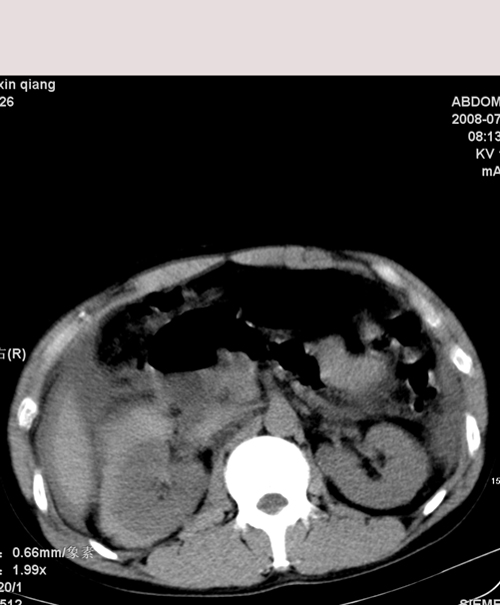

以下是引用muzi888在2008-7-15 10:45:00的发言:[br]大量腹腔积液,气腹,肾皮质弧形高密度影,诊断;1 空腔脏器穿孔 2 右肾包膜下血肿

以下是引用随光逐影在2008-7-15 11:18:00的发言:[br]考虑为:1)腹部空腔脏器穿孔。2)右肾破裂并肾包膜下血肿,肾盂积血。3)腹水(血)。